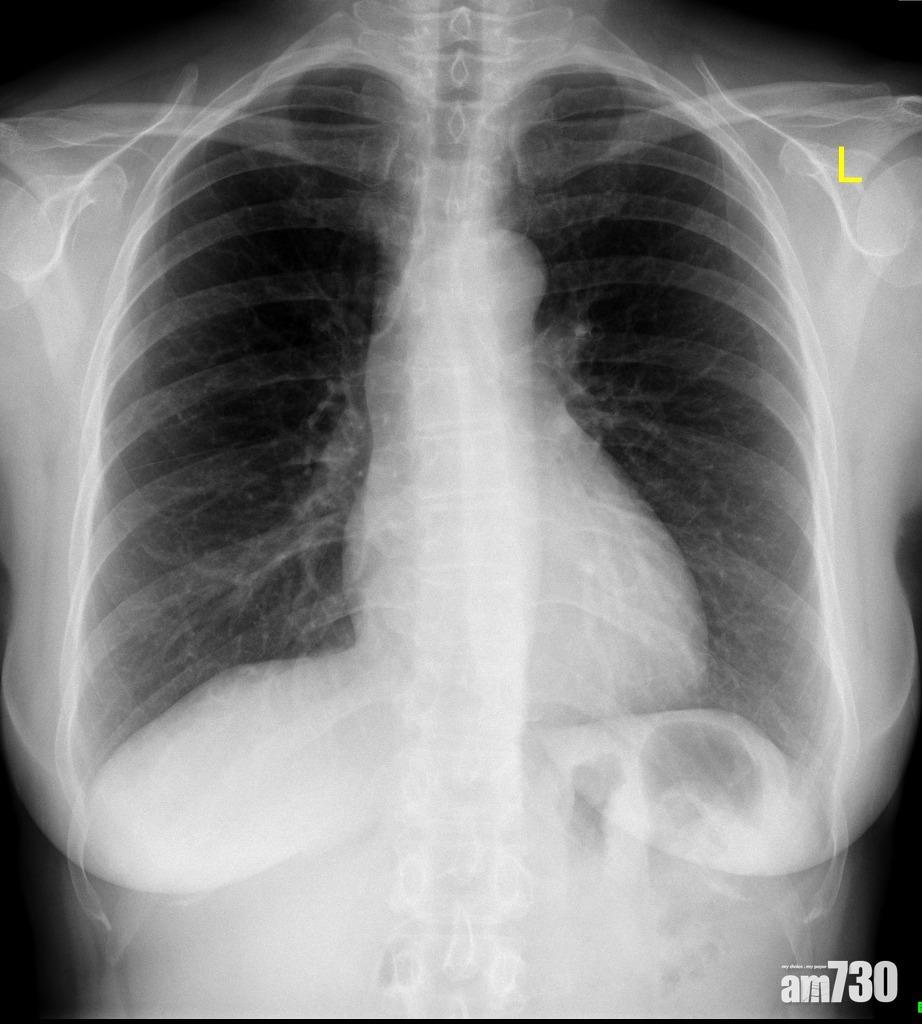

照一次胸肺X光大約接受了0.05毫希沃特輻射。

做甚麼會接受了多大劑量的輻射,可參考此圖。

那麼在多少劑量的輻射下才會出現有關影響?如果受到多達10希沃特的劑量,又沒有適當處理便會有生命危險;而超過1希沃特便已經出現急性傷害,出現嘔吐、脫髮、疲倦徵狀;0.1至1希沃特雖不致縮短壽命,但可能引起癌症、遺傳病等;若少於0.05希沃特,並不會構成顯著影響。作為參考,照一次胸肺X光大約為0.05毫希沃特(1毫希沃特=0.001希沃特),坐飛機來回香港和倫敦大約0.08毫希沃特。